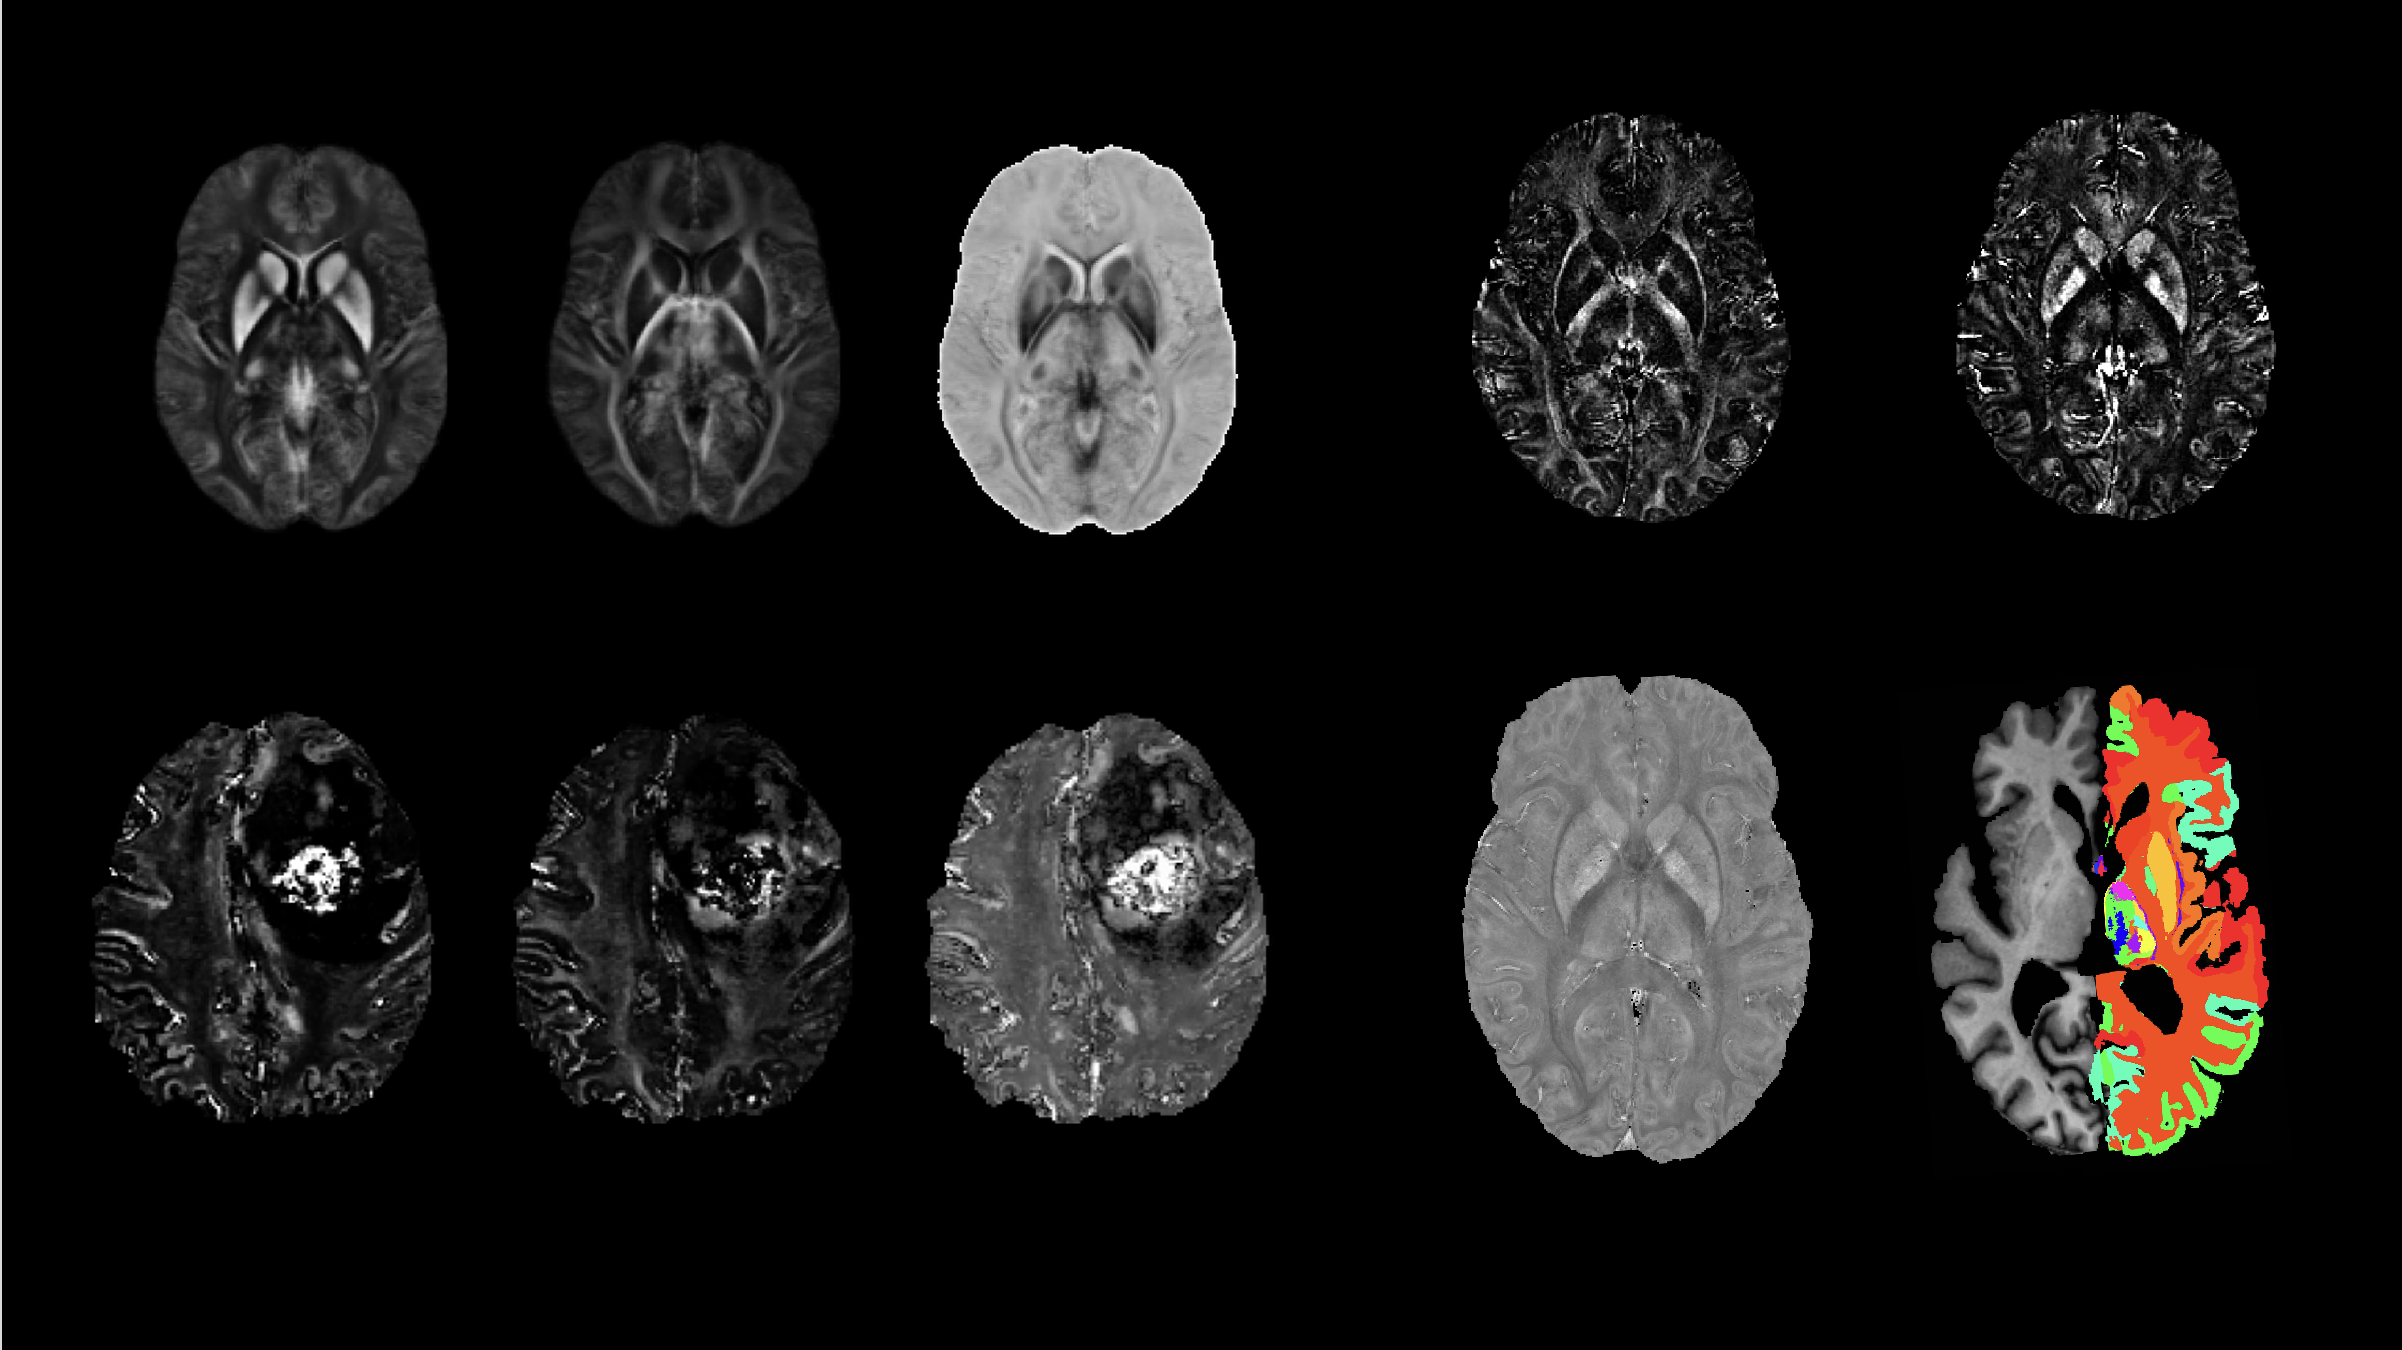

Magnetic susceptibility is a physical quantity that defines how strongly a material can be magnetized by an applied magnetic field. We are developing MRI-based methods to measure the spatial distribution of magnetic susceptibility in biological tissues.

7 T MRI

We are involved in a project funded by NIH BRAIN Initiative to develop a next-generation human brain MRI scanner that utilizes 7-Tesla magnetic field. We develop hardware and pulse sequences for the scanner. We also investigate how this NexGen 7T scanner can be best utilized to study brain diseases and disorders.

Image Reconstruction

We employ signal processing, optimization and AI techniques to improve the image quality of MRI scans. We combine these techniques with physical principles of MRI to generate new image contrasts and study the brain physiology and diseases.